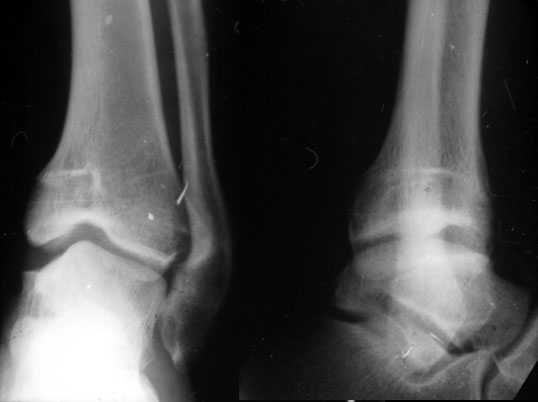

Аппаратом можно сделать все минимально инвазивно и травматично, вырастить клиновидный регенерат после чрескожной остеотомии через один или два разреза 0,5 см. В приложении похожий по локализации случай, только более давние последствия травмы с замыканием части зоны роста, деформация побольше, плюс укорочение голени было.

Уважаемый Александр то что вы показали это интересно, но это два разных случая. В ваших снимках большая деформация, которая требует выращивания массивного регенерата, поэтому здесь согласен лучше аппарат, а представленном случае дефект будет небольшой поэтому накостный синтез решит все проблемы за 2 недели без ключей 8*10 в течении 3-5 месяцев.Зачем себе создавать головную боль.

Согласен, тут деформация меньше, но все-таки заметная, почти 20 градусов. Я бы устранял ее как на приложенной картинке.